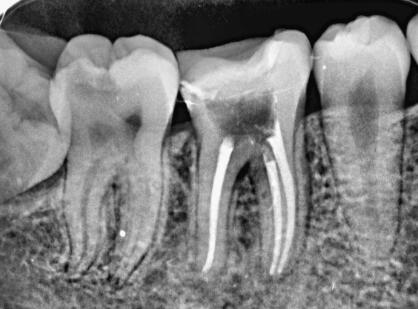

西安是一座文化底蕴十分丰富的城市,拥有各种各样的美食。美食吃多了往往容易产生一些牙齿问题,因此就需要进行根管治疗,男女老少对于牙齿的保护意识还需要加强。根管治疗在牙科医生之间常见,相信很多小伙伴对于这个词也并不陌生。口腔临床上很常见的一种治疗方式。根管治疗术是通过清除根管内的坏死物质,进行适当的消毒,充填根管很多不同年龄段的人们都可能做过。很多小伙伴很关心根管治疗的价格情况以及能不能走医保报销流程,下面就让小编为大家介绍一下根管治疗所需要的具体步骤以及操作方法。以及大家关心的怎么走医保报销。

通常情况下,根管治疗需要就诊2-4次,耗时2-3周左右,一般被诊断为牙髓炎或者根尖周炎的牙齿需要根管治疗。如果需要做根管治疗,请到当地正规公立医院口腔牙体牙髓科就诊,检查和治疗。定期前往医院复查,日常生活中做好牙齿的清洁工作还是很重要的。

很多小伙伴担心根管治疗会不会很疼,其实大可不必担心。涉及到牙神经方面的牙齿问题,牙科医生都会打上麻药,感受不到牙齿的疼痛,就算是牙齿由于蛀牙缺失了一大部分,也不用担心。如果没有触及到神经直接清洗干净,消毒后填充就可以了。如果伤到了牙齿神经,那么就需要根管治疗了。治疗时间可能比较长,医生需要观察情况,视情况来判断。一旦出现持续的疼痛等问题,需要第一时间前往医院向医生寻求帮助。